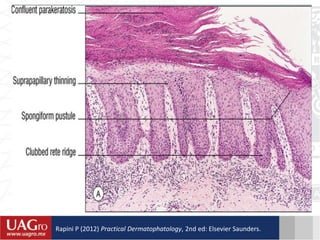

DATOS HISTOPATOLÓGICOS

• Hiperqueratosis/paraqueratosis.

• Papilas dérmicas próximas a la superficie y muy vascularizadas. Se

observan capilares tortuosos y ectásicos en proliferación o

hipertróficos.

• Capa córnea formación de microabscesos de Munro-Sabouraud con

neutrófilos picnóticos

• Capa espinosa, formación ocasional de la pústula espongiforme de

Kogoj.

• Dermis superficial  vasodilatación e infiltrados inflamatorios

moderados, constituidos mononucleares.

• Adherencia celular está limitada a los desmosomas, por  neta de

glucoproteínas en la superficie celular.

Rapini P (2012) Practical Dermatophatology, 2nd ed: Elsevier Saunders.

DATOS HISTOPATOLÓGICOS • Hiperqueratosis/paraqueratosis. •Papilas dérmicas próximas a la superficie y muy vascularizadas. Se observan capilares tortuosos y ectásicos en proliferación o hipertróficos. • Capa córnea formación de microabscesos de Munro-Sabouraud con neutrófilos picnóticos • Capa espinosa, formación ocasional de la pústula espongiforme de Kogoj. • Dermis superficial  vasodilatación e infiltrados inflamatorios moderados, constituidos mononucleares. • Adherencia celular está limitada a los desmosomas, por  neta de glucoproteínas en la superficie celular.